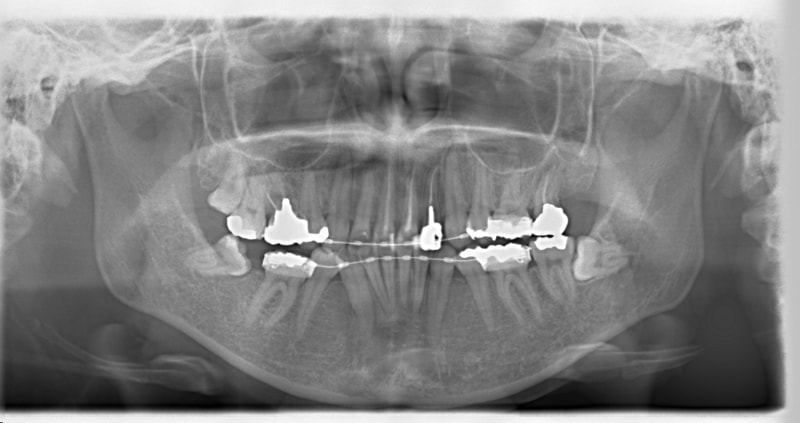

右下7番欠如歯(保存不可能歯につき抜歯)右下8番利用

治療法:フルパッシブブラケット:クリアスナップ